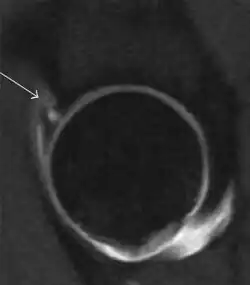

Most of the angles and measurements described in the plain radiograph section can be accurately reproduced on MRI. In addition, the superiority of MRI resolution with intra-articular contrast allows detection of labral and chondral abnormalities that may influence the choice of medical, percutaneous, or surgical management (Figure 9).[1]

Figure 9:

Sagittal T1 weighted image showing anterosuperior labral tear.[1] -

Sagittal T1 weighted image showing chondral lesion.[1] -

Sagittal CT-arthrography showing posteroinferior chondral injury.[1] -

Coronal CT-arthrography (d) showing ligamentum teres tear.[1]

MR arthrography has proven superior in accuracy when compared to native MR imaging. It is considered the best technique to assess the labrum. Knowledge of the normal variable morphology of the labrum helps to differentiate tears from normal variants. A triangular shape is most commonly seen in 66% of asymptomatic volunteers, but round, flattened, and absent labra can also be found in asymptomatic populations. MR arthrography has demonstrated sensitivity over 90% and specificity close to 100% in detecting labral tears. Loose bodies are demonstrated as filling defects surrounded by the hyperintense gadolinium.[1]

Association between labral tears and chondral damage has been demonstrated. This underscores the interaction between cartilage and labrum damage in the progression of osteoarthritis. Chondral damage to the posteroinferior part of the acetabulum as a contrecoup lesion occurs in approximately one-third of pincer cases secondary to persistent abutment on the anterior part of the joint leading to a slight posteroinferior subluxation. This is considered a bad prognosis sign.[1]

MR arthrography can also demonstrate ligamentum teres rupture or capsular laxity, which are debated causes of microinstability of the hip. Elongation of the capsule or injury to the iliofemoral ligament or labrum may be secondary to microtrauma in athletes. MR can demonstrate abnormalities in these cases, such as increased joint volume or a ligamentum teres tear (Figure 9).[1]